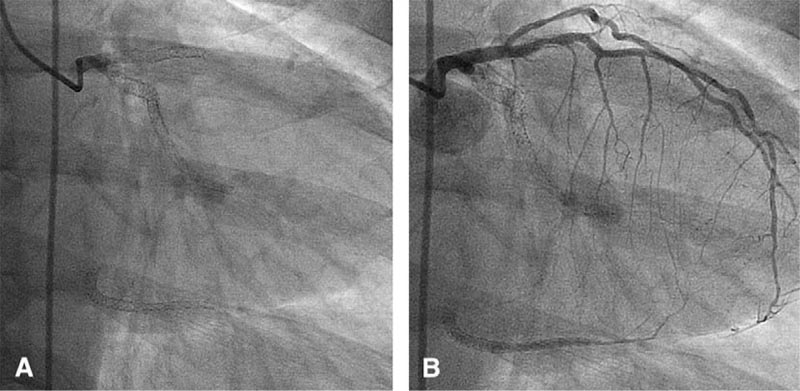

1. Правая коронарная артерия: 1,2,3 сегменты, стеноз с переходом в окклюзию (хроническую, о чем говорят мощная сеть коллатералей и старый инфаркт в анамнезе). Окклюзия с тупым концом (blunt stump), окружена коллатералями (bridging). За хронической окклюзией сегмент визуализируется, но в месте окклюзии отходит одна ветвь больше 1,5 мм, кроме того есть мелкие ветви 0,1,0 по Медина, есть извитость.